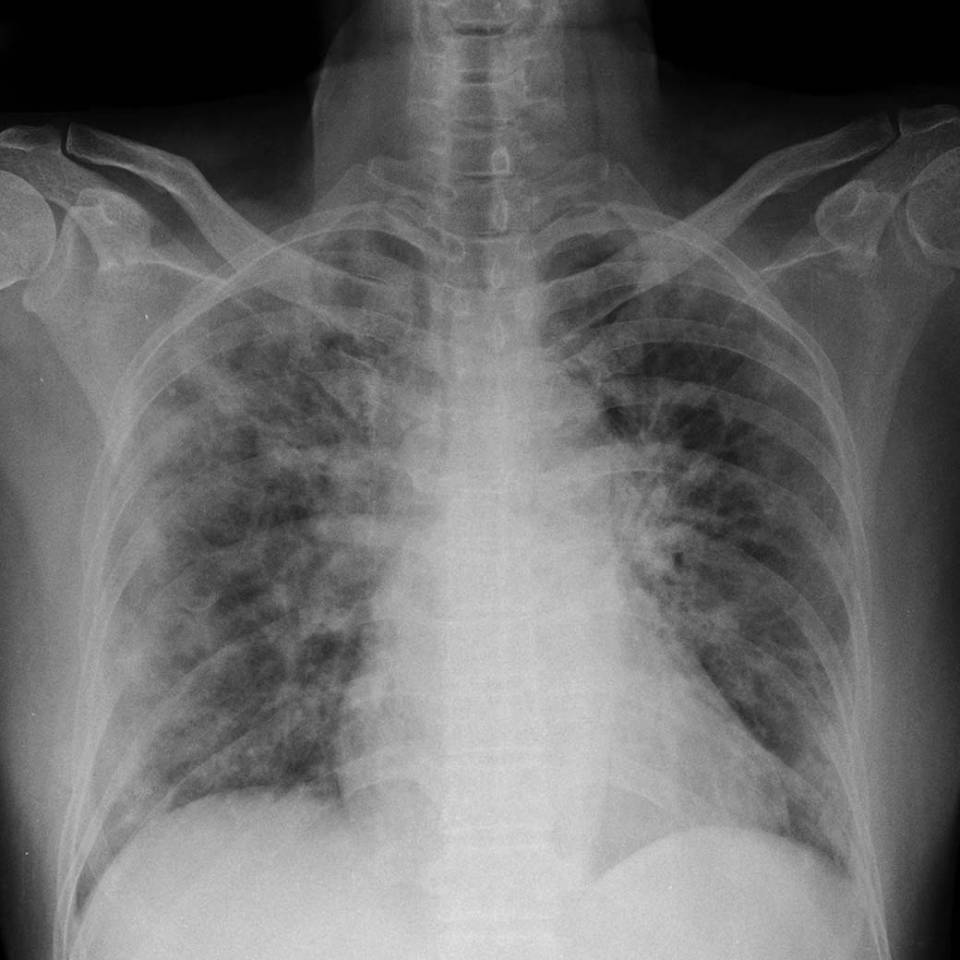

Estudios de imagen

Análisis detallado de los estudios de imagen de tórax (TAC, Radiografías, Gamagrama, V/Q, entre otras)